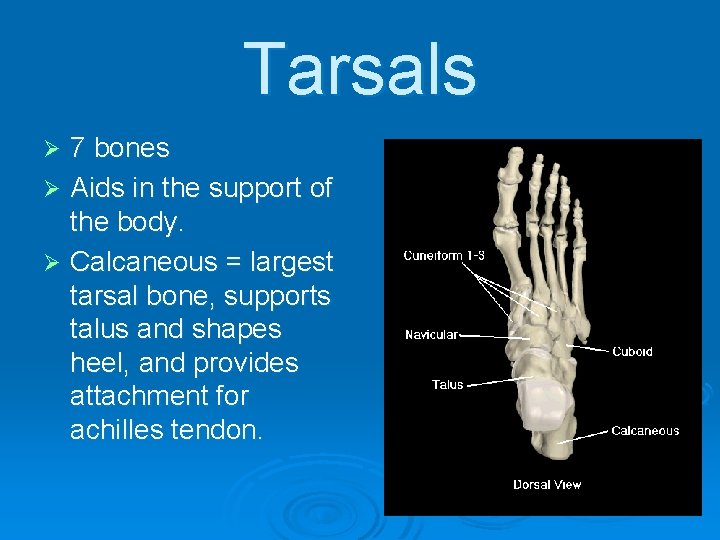

Tarsals 7 bones Ø Aids in the support of the body. Ø Calcaneous = largest tarsal bone, supports talus and shapes heel, and provides attachment for achilles tendon. Ø